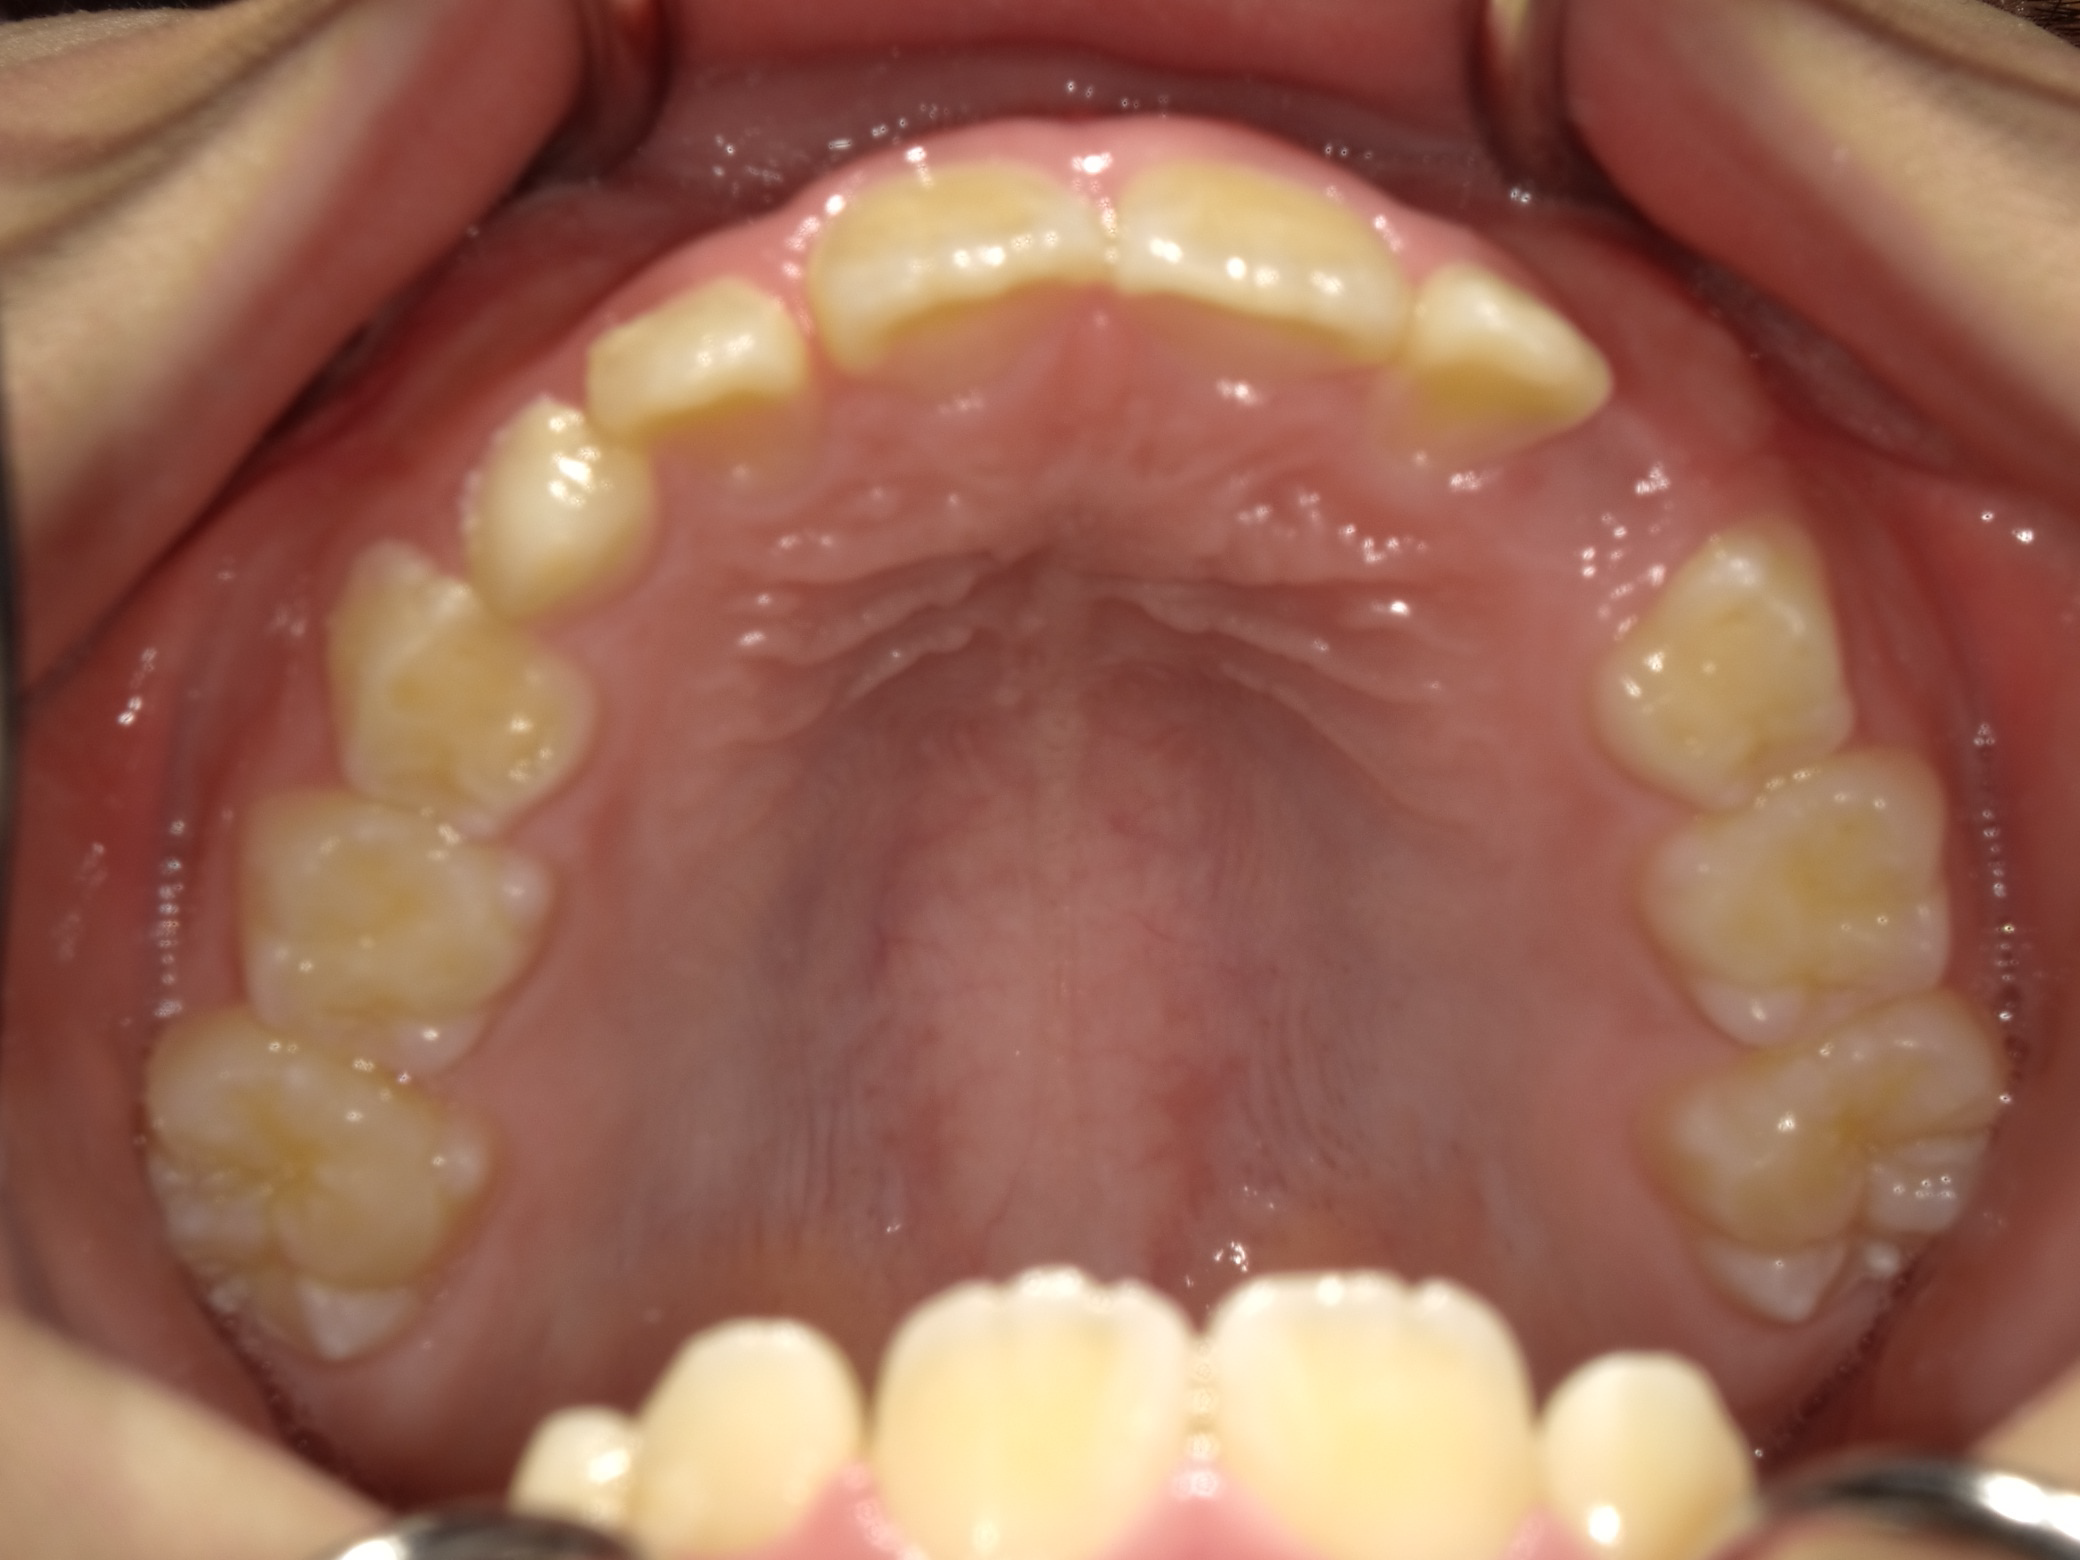

1期矯正の経過

時間はかかりますが、だいぶ凸凹が改善してきました。しかしまだ正面か見ると下の歯が見えません。

今回は上の歯が出過ぎているというより、下の顎は引っ込みすぎていると診断し、下顎を前に誘導する装置を使用します。

装置使用前後の比較

前歯に若干の凸凹はありますが、あとは2期治療で簡単に改善可能です。